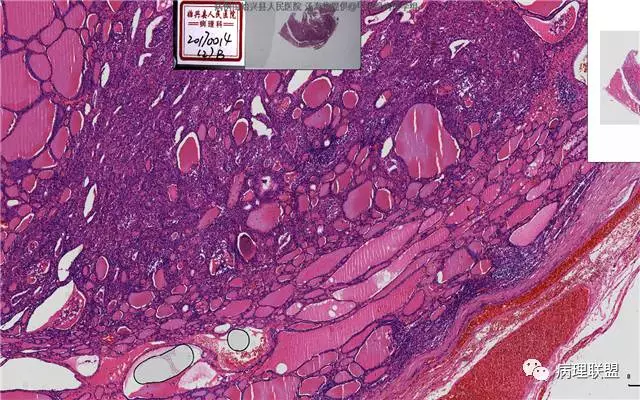

患者,女,45岁,发现双侧甲状腺肿物半月余。大体所见:左侧甲状腺肿物:4.3*5*4cm肿物一个,包膜完整,光滑,质脆,中央见出血。右侧甲状腺组织:3*1.6*1.5cm及1*1*0.8cm组织两块,其中较大的组织切开见内有0.8cm及1.2cm两个,质硬,灰白色,界不清,较小的,切开见灰黄色,质脆。